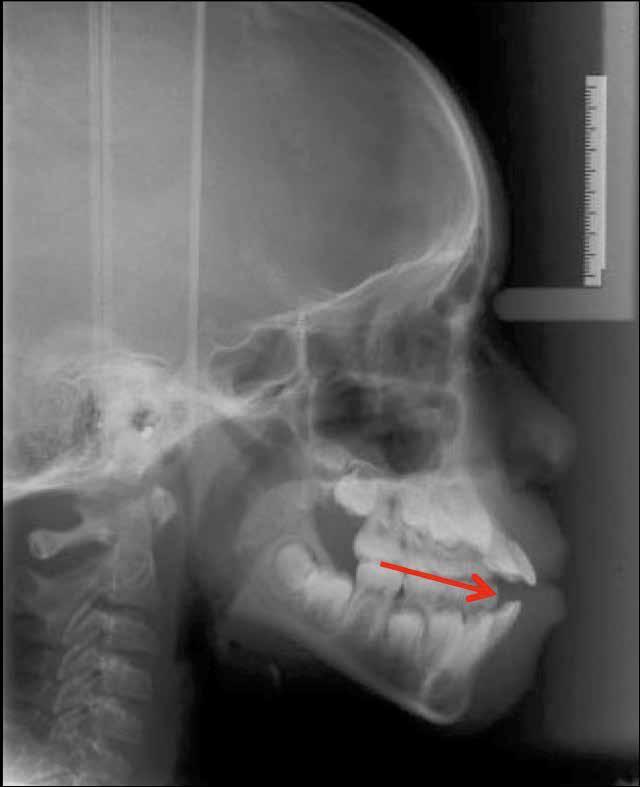

A 10 éves férfi páciens a felső frontfogai késői/nem megvalósuló előtörése miatt kereste fel a rendelőnket. A klinikai és a radiológiai vizsgálat során a jobb felső nagymetszőfog impakcióját észleltük (1. ábra). A fog horizontális tengelyállással és dilacerált gyökérrel rendelkezett. A felső dentális középvonal a fogak vándorlása miatt jelentős mértékben elcsúszott. A bal felső kismetszőfog is rendkívül kedvezőtlen pozícióba került.

1. b ábra: A panoráma röntgenfelvételen megfigyelhető a teljes impakcióban lévő jobb felső nagymetszőfog. 1. c ábra: A CBCT felvétel is igazolja a jobb felső nagymetszőfog impakcióját.